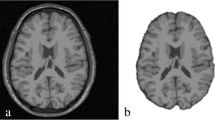

The performance of medical image segmentation is generally affected by the parameters of the adopted method and noise. To overcome these issues we introduce in this paper a novel segmentation approach of brain MRI using a region based-active contour model and evolutionary algorithm and without performing any pre-processing step. Our main objective is to accurately extract edges, resolve the intensity inhomogeneity problem and overcome manifestations of noise. Chan and Vese model was adopted by introducing a local similarity factor based on Bilateral filter principle (LSFB). The adjustment of our functional energy parameters was achieved using a multi-population genetic algorithm (MPGA) which can display better search performance than serial single population models, in terms of the quality of the solution found, effort and processing time. We selected Brain MRI from Oasis and Brainweb data base with different noise type. The initialization of the active contour was totally random. A comparison of segmentation results with Chan and Vese model and active contour model with a locally computed signed pressure force (SPF) of Akram and his team reveals a clear efficiency of our proposed approach.

F. Z. Belgrana and N. Benamrane, “A fast and robust segmentation of magnetic resonance brain images using a combination of the pyramidal approach and level set method,” Int. J. Imaging Syst. Technol. 27 (2), 182–182 (2016).